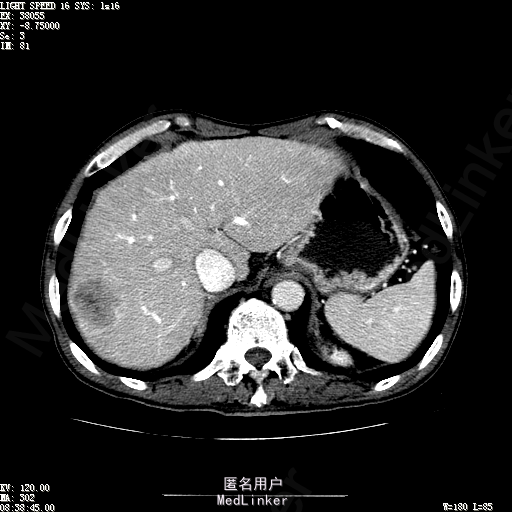

查体:体温36.3℃,脉搏76次/分,呼吸18次/分,血压120/80mmHg。神志清晰,肝病面容,皮肤粘膜颜色正常无黄染,全身皮肤未见皮疹、瘀点及紫癜,肝掌阳性,未见蜘蛛痣,浅表淋巴结未触及。巩膜无黄染,结膜正常。双肺呼吸音清,无胸膜摩擦音。心率:76次/分,心律齐,心音正常,无杂音,无心包摩擦音。腹平坦,无腹壁静脉曲张,未见胃肠型及蠕动波,双侧腹股沟可见手术瘢痕,脐部正常。触诊:无压及痛反跳痛,无腹肌紧张,无腹部包块。肝脾肋下未触及,Murphy征阴性,肾未触及,移动性浊音阴性。肝肾区叩击痛阴性,无脾区叩击痛。听诊:肠鸣音正常,4次/分,无气过水声。脊柱无侧弯,脊柱活动度正常,棘突正常,四肢正常,关节正常,无下肢水肿,无下肢静脉曲张,无杵状指趾。扑翼样震颤阴性。 门诊化验ALT9U/L,AST21U/L,HBVDNA<1.0E+03IU/mL,HBsAg1138IU/mL,WBC6.2x10^9/L,RBC3.92x10^12/L,PLT167x10^9/L,AFP28.95ng/ml,AFU 29U/L,彩超示肝右叶肝回声,大小约5.1*3.5cm,Fibroscan:脂肪变:163硬度10.8。 CT如下图

诊断:1、乙肝肝硬化 活动性 代偿期 原发性肝癌 2、胃溃疡 3、十二指肠球部溃疡 处理:血管介入治疗:手术者术前查看患者相关情况:化验回报:血细胞分析(五分类):*白细胞计数 8.1 10^9/L、*红细胞计数 4.00 10^12/L↓、*血小板计数 202.0 10^9/L、*血红蛋白 136 g/L,肝功酶谱:*丙氨酸氨基转移酶 5 U/L、天门冬氨酸氨基转移酶 22 U/L、*白蛋白 37.6 g/L、*总胆红素 17.8 umol/L,肾功能检测:*尿素 5.79 mmol/L、*肌酐 67.1 umol/L,凝血五项:凝血酶原时间 10.7 秒↓、凝血酶原百分活动度 93.3 %,甲胎蛋白测定:甲胎蛋白 30.30 ng/mL↑。患者病情平稳,今日术前准备,签署相关文件。 手术简要经过:患者平卧位,以右侧腹股沟区为中心常规消毒、铺巾、利多卡因局麻。改良Seldinger法逆行穿刺右侧股动脉成功,置入5F血管鞘。经血管鞘造影,见髂外动脉明显迂曲,经鞘送入超滑导丝,退出原5F血管鞘,换入5F长25厘米血管鞘。沿导丝送入肝管,将管头送入腹腔干,进一步送至肝右动脉。经正位、右前斜30°造影,明确肝右叶膈顶一处较大肿瘤染色,S5段一处较小肿瘤染色。以微导管超选S6段肝动脉干,经多角度造影明确为肿瘤供血动脉,注入混悬液(碘化油10毫升+雷替曲塞2毫克)3毫升,明胶海绵颗粒1/12支。再以微导管超选S7段肝动脉干,造影明确为肿瘤供血动脉,注入混悬液2毫升,明胶海绵颗粒1/20支。再以微导管超选S8段分支,造影明确为肿瘤供血动脉,注入混悬液2.8毫升,明胶海绵颗粒1/12支。再以微导管超选S5段肝动脉分支,造影明确为较小肿瘤供血动脉,注入混悬液0.8毫升,明胶海绵颗粒1/30支。退出微导管。经肝右动脉注入奥沙利铂100毫克。退出肝管。拔出血管鞘,局部压迫5分钟。加压包扎。